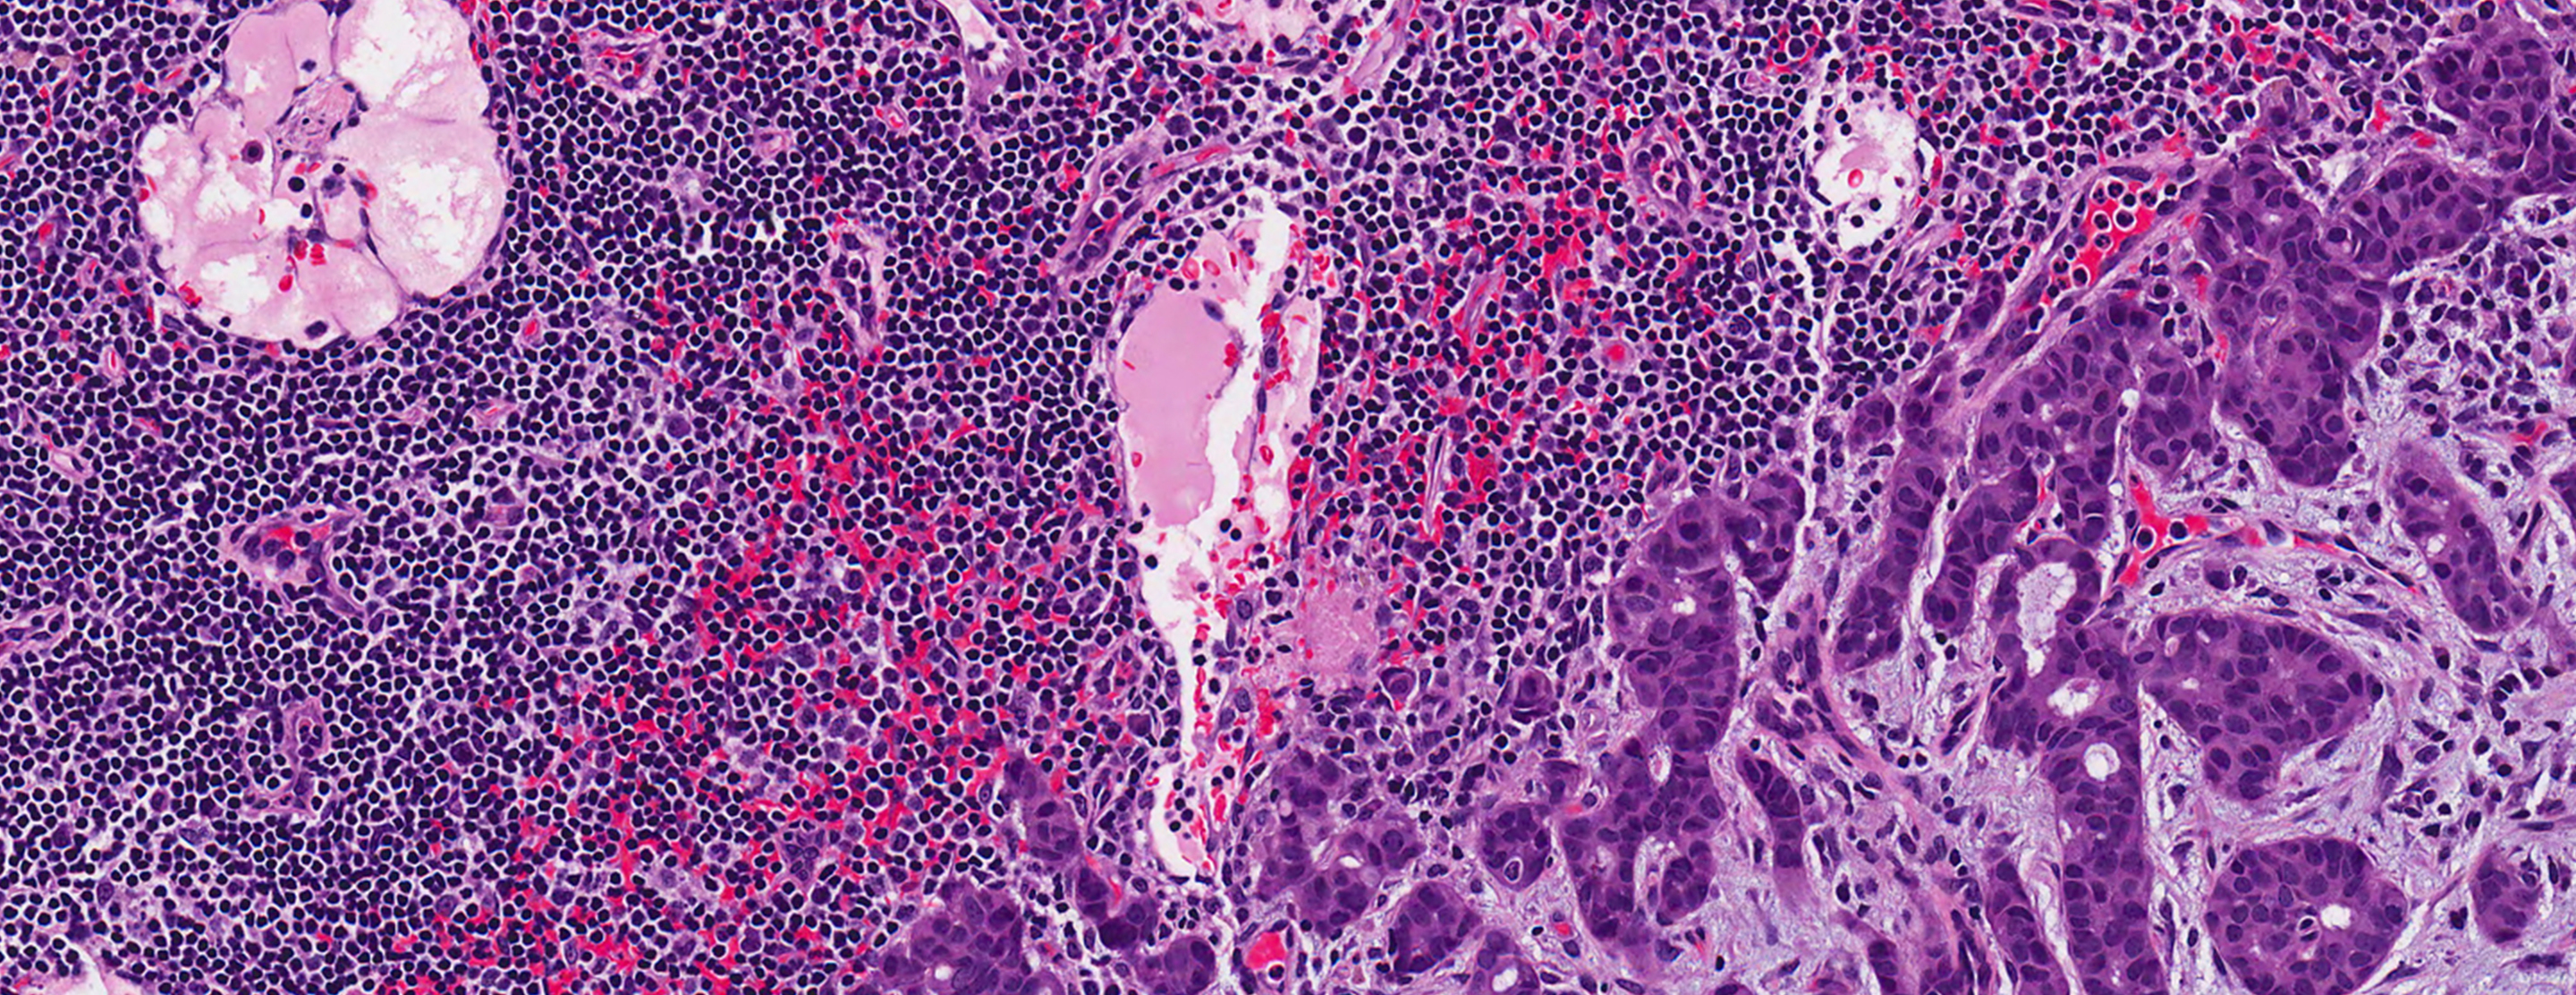

The tissue samples are sent to a pathologist to be examined.

A normal result means there is no sign of cancer.

If the biopsy shows benign breast tissue without cancer, you will likely not need surgery.

Biopsy results may show abnormal conditions such as:

- Atypical ductal hyperplasia

- Atypical lobular hyperplasia

Intraductal papilloma - Flat epithelial atypia

- Radial scar

- Lobular carcinoma-in-situ

- Fibroepithelial lesion

- Mucocele-like lesion